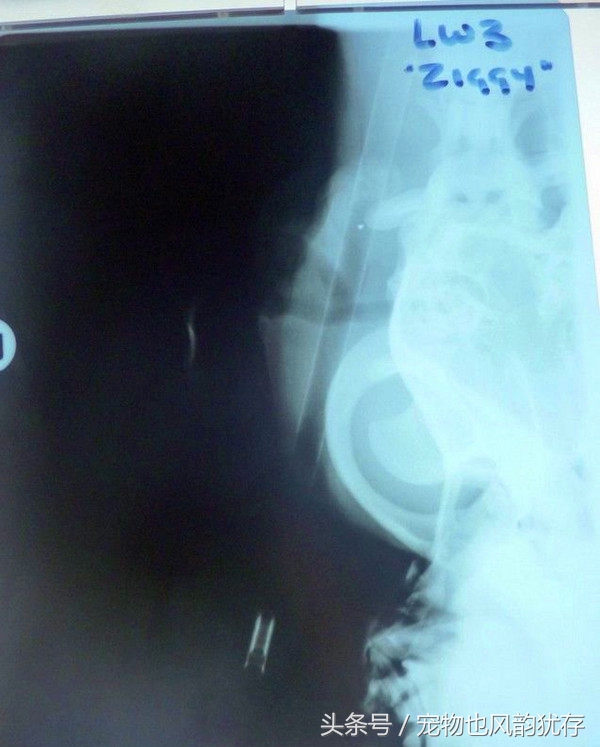

这是医院为宠物狗拍摄的X光,可以看出,弓箭的确是从狗狗头部穿过!医护人员也觉得神奇,这狗狗在受伤后还懂得自己去医院看医生求救!非常难得,医院这边也将和动物协会联系,看怎么妥善处理这只狗狗的后期生活。